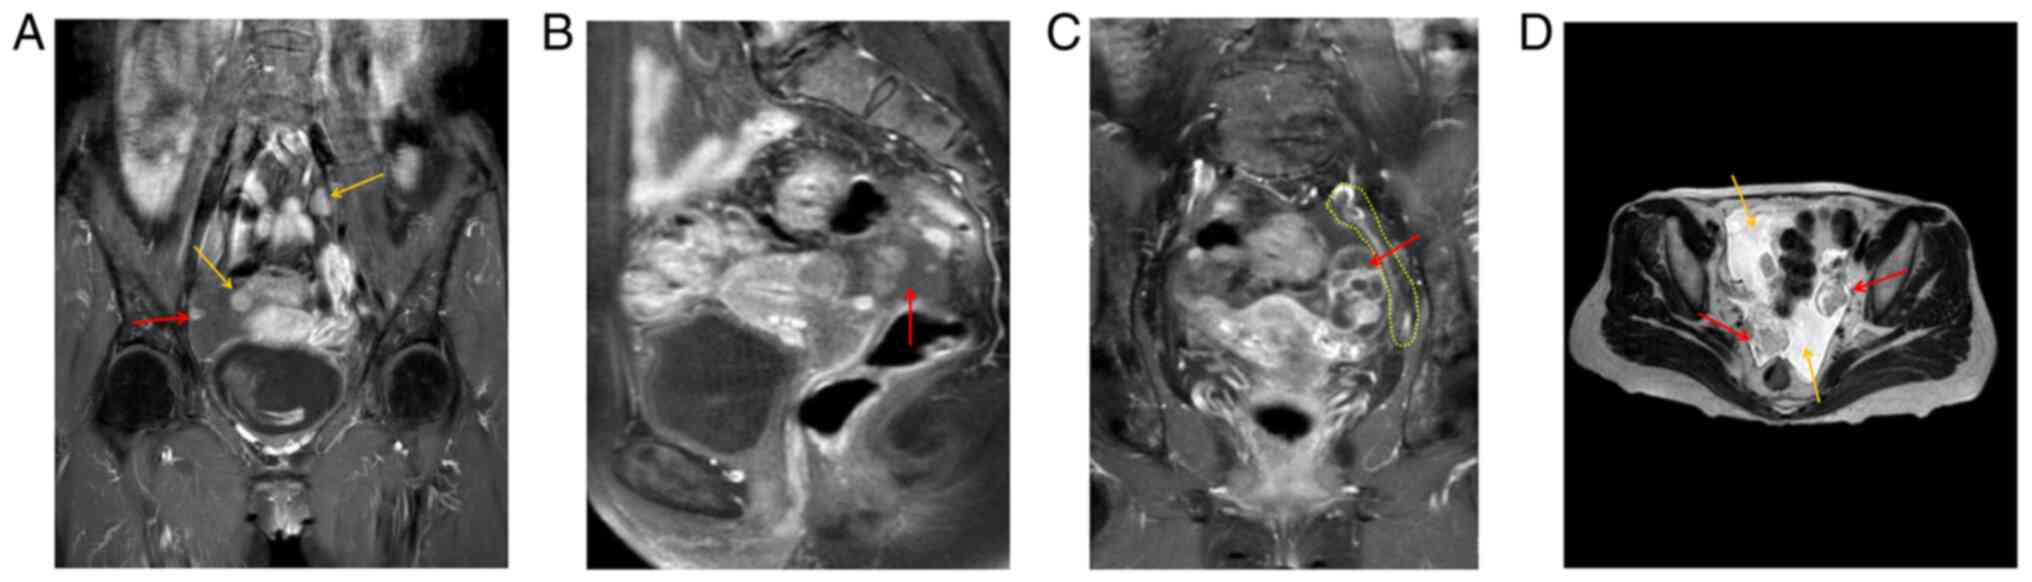

Preoperative MRI indicated two enlarged lymph nodes in the pelvic cavity (yellow arrows), and peritoneal lesions (red arrow) (Fig. 2A). The right adnexal area was irregular in shape, 27x43x28 mm in size, and DWI indicated high signal intensity, with uneven enhancement of the right lesion (red arrow) (Fig. 2B). An elliptical cystic solid lesion was present in the left adnexal area of the pelvis, the size of which was 31x26x40 mm (red arrow) and the peritoneum was thickened (yellow dotted line) (Fig. 2C). T2WI indicated two lesions (red arrows) in the left and right adnexa area and a certain amount of pelvic fluid collection (yellow arrows) (Fig. 2D).

Figure 2

Preoperative MRI findings. (A) Preoperative MRI indicated two enlarged lymph nodes in the pelvic cavity (yellow arrows) and peritoneal lesions (red arrow). (B) The right adnexal area was irregular in shape and 27x43x28 mm in size, and diffusion-weighted imaging indicated a high signal intensity, with uneven enhancement of the right lesion (red arrow). (C) There was an elliptical cystic solid lesion of 31x26x40 mm (red arrow) in the left adnexal area of the pelvis and peritoneum exhibited thickening (yellow dotted line). (D) T2-weighted MRI indicated two lesions (red arrows) in the left and right adnexa area and a certain amount of pelvic fluid collection (yellow arrows).